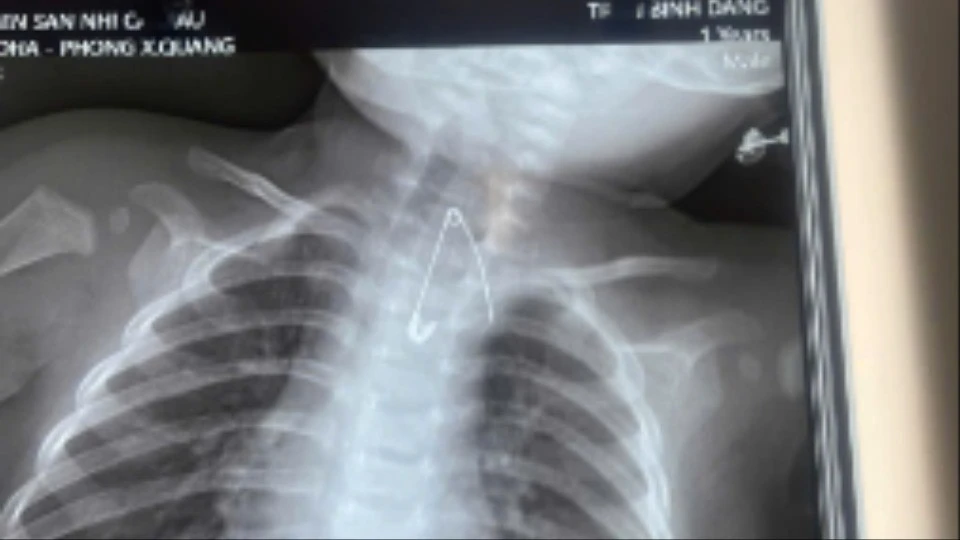

Trẻ bị thủng tá tràng vì nuốt que kẹo mút

Hai ca bệnh nhi nguy hiểm ở Cà Mau với dị vật thủng tá tràng và sát động mạch chủ đã được các bác sĩ xử lý thành công, đảm bảo an toàn tính mạng.